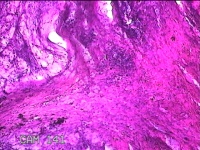

会阴部结节

性别

男

年龄

34岁

临床诊断

会阴部良性肿瘤

一般病史

发现会阴部结节1周。

标本名称

大体所见

灰白粉红色组织1.3x1.2x0.3cm一块,表面光滑,切面灰白粉红色。质软。

图1